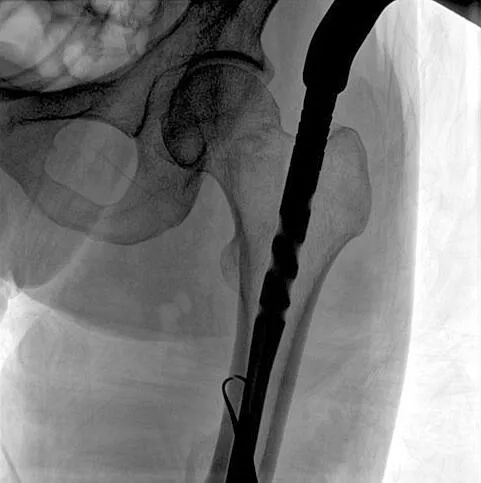

患者:男性,43歲,左股骨干骨折髓內(nèi)釘內(nèi)固定術(shù)

醫(yī)院:南京應(yīng)天骨科醫(yī)院

術(shù)中使用普愛醫(yī)療大平板一體式C形臂進(jìn)行透視,判斷骨折情況及克氏針、髓內(nèi)釘?shù)冉饘僦踩胛锏奈恢?,進(jìn)行調(diào)整。C形臂準(zhǔn)確的術(shù)中定位,大大縮短了手術(shù)的時(shí)間,減輕了患者的痛苦,輔助手術(shù)順利完成。

在進(jìn)行髓內(nèi)釘內(nèi)固定術(shù)時(shí),醫(yī)生需要同時(shí)觀察到入釘點(diǎn)和骨折部位的情況,普愛醫(yī)療大平板一體式C形臂采用30CM×30CM的平板探測器,能夠呈現(xiàn)更廣闊的成像面積,滿足大部分長骨髓內(nèi)釘內(nèi)固定術(shù)的攝片需求。

術(shù)中定位準(zhǔn)確、出血量少,術(shù)后影像顯示股骨移位糾正,恢復(fù)良好力線,手術(shù)效果良好。